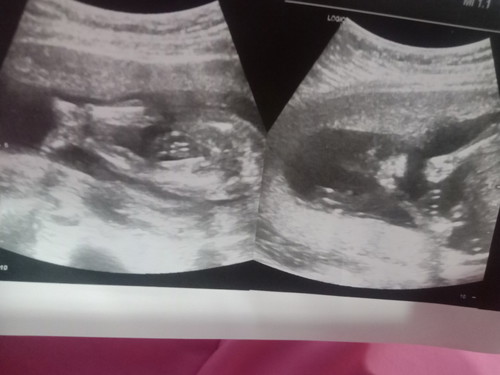

19 Wเข้า20 หมอบอกยังไม่เห็นเพศ 16 ธ.ค นี้. มาตรวจใหม่ลุ้น หญิง. เเอบดีใจ. เเม่ๆลุ้นออกบ้างมั้ยค่ะ

มองไม่ออกเลยจ้า ขนาดตอนเราซาว หมอบอกตรงนี้คือแคมนะ ได้ผู้หญิงค่ะ แต่ดูยังไงก็ไม่รุ้ว่าตรงไหนแคม😆😆😆